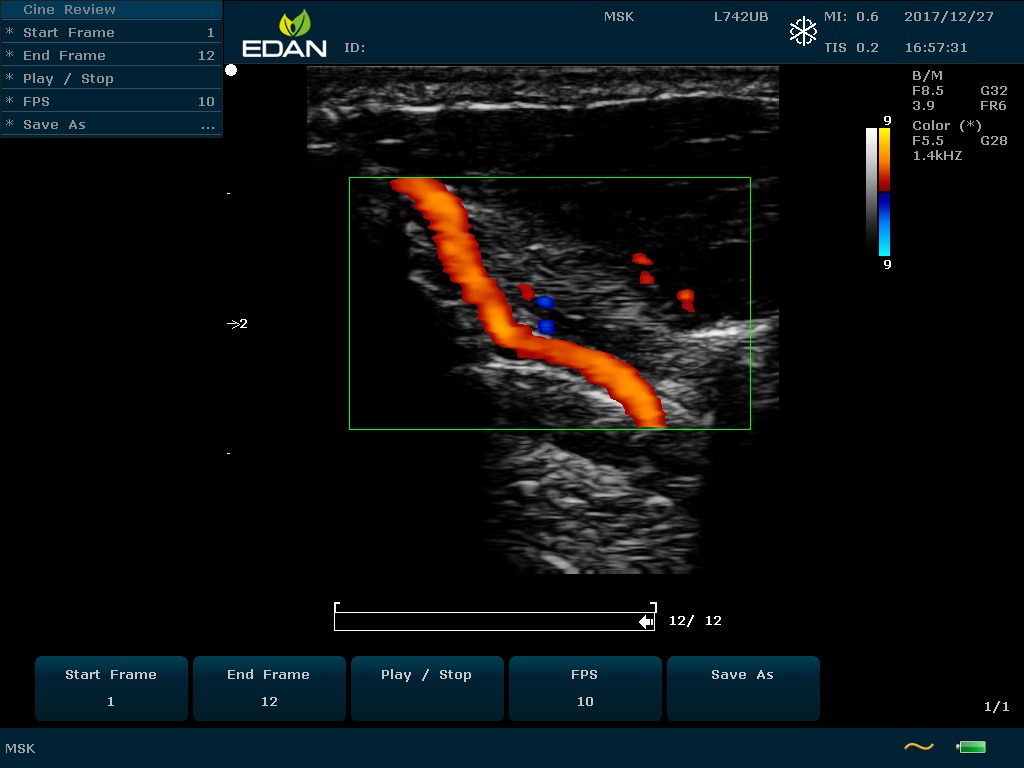

Особенность U60 Edan — расширенное применение. Ультразвуковой аппарат рекомендован для абдоминальных исследований, гинекологии и акушерства, кардиологии, педиатрии, урологии, изучения малых органов, сосудов. Для U60 Edan используются конвексные, линейные, фазированные и внутриполостные датчики.

Передовые технологии позволяют повысить качество визуализации в несколько раз. УЗИ-аппарат U60 Edan отличается возможностью быстрой настройки визуализации. Специальные функции позволяют моментально отображать данные за счет быстрой оптимизации параметров. Режимы визуализации: B-mode, M-mode, Color Doppler, Power Doppler Imaging, Pulsed Wave Doppler, Continuous Doppler.

Для улучшения качества изображений в В-режиме быстро регулируются все необходимые параметры. Быстрые инструменты изображения: LowFlow, Medium Flow, High Flow, Detail, Soft, High Contrast.